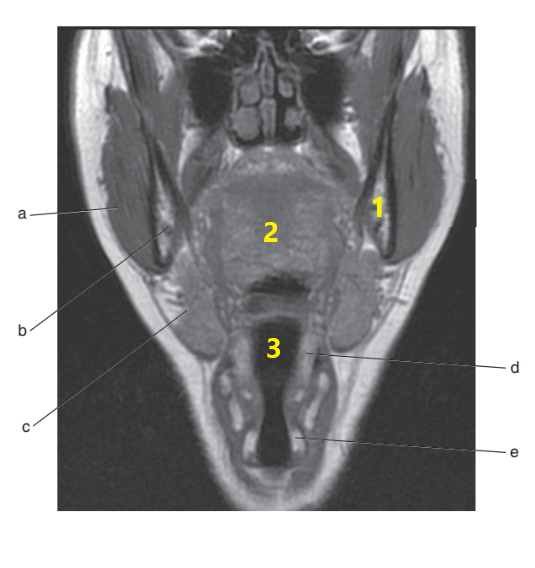

Submandibular gland

Thyroid gland

What is # 1 ?

Tongue

Masseter muscle

Mandible

Parotid gland